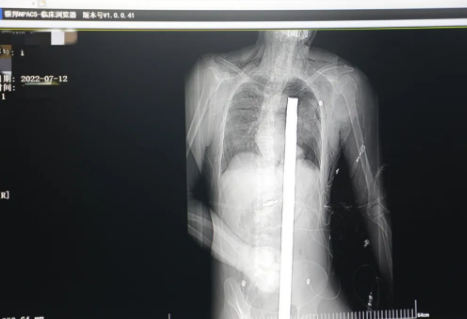

時(shí)間就是生命!此時(shí),西安國際醫(yī)學(xué)中心醫(yī)院展開了一場與生命賽跑的搶救,第一時(shí)間開辟綠色通道,急診X光片及CT顯示:異物經(jīng)會陰部貫穿盆腔、腹腔到達(dá)左側(cè)胸腔主動脈弓水平。醫(yī)院創(chuàng)傷中心立即啟動應(yīng)急預(yù)案,劉延彤副院長親臨指揮,下午17點(diǎn)48分,當(dāng)患者被送達(dá)手術(shù)室,胸外、心外、肝膽外科、胃腸外科,泌尿外科及麻醉科等多學(xué)科專家聯(lián)手對這名工友進(jìn)行“縱劈胸骨 前外側(cè)開胸探查 氣管及主支氣管修補(bǔ) 肺修補(bǔ) 血胸清除 開腹探查止血 腹膜后及盆腔探查......”手術(shù)。

情況緊急!術(shù)中探查后發(fā)現(xiàn),長120cm直徑3cm的螺紋鋼經(jīng)患者右側(cè)會陰部穿入,傷及直腸,途徑膀胱后方,左側(cè)髂總動靜脈之間傷及左腎后,經(jīng)胰腺后方在肝脾之間穿破膈肌,在下肺靜脈前方穿入左肺穿破氣管及左右主支氣管膜部,止于主動脈弓下水平,穿入體內(nèi)的部分達(dá)到75cm。